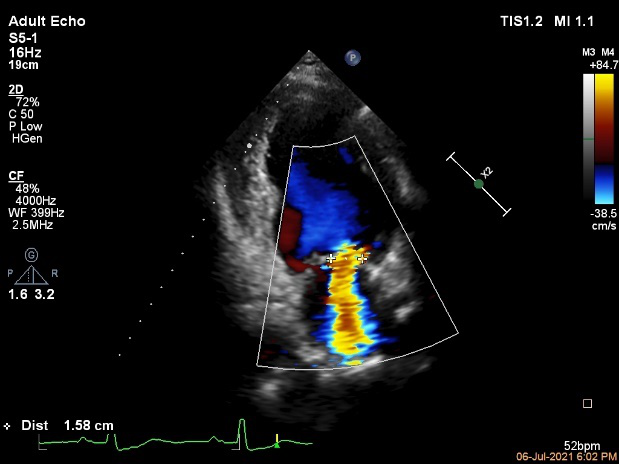

病例四简介

患者为70岁男性,主因“间断胸闷、气短15年,加重1年”入院,患者15年前与活动后出现胸闷、气短症状,无胸痛、心悸,无夜间阵发性呼吸困难及双下肢水肿,1年来上述症状加重,偶有夜间不能平卧。

当地行超声提示:“二尖瓣中-重度关闭不全,射血分数减低”,予药物治疗,上述胸闷、心悸、喘憋症状仍间断出现。10月前因胸痛不缓解,当地医院诊断为“急性心肌梗死”,行球囊扩张术,术后活动仍存在胸闷、气促症状。6月前余当地医院查超声心动:LVEDD74mm,LVEF 31%,二尖瓣重度反流。

入院诊断:

心脏瓣膜病 二尖瓣重度关闭不全 心功能III级(NYHA分级);冠状动脉粥样硬化性心脏病 陈旧性心肌梗死,高血压。

术前讨论:

患者老年女性,二尖瓣重度关闭不全诊断明确,患者存在心力衰竭症状及体征,目前经积极药物抗心衰治疗,其心衰症状改善不明显,左室增大,考虑二尖瓣重度关闭不全对患者心功能影响较大,但其二尖瓣置换STS评分15.098%,经综合评估后,认为该患者有行MitraClip指征。

术前超声诊断:

长轴:左室下后壁节异,LAV:101ml,LVEDV:239ml

Bicom:MR(重度),返流束宽15.8mm,返流面积10.6cm²

PISA法定量EROA:0.69cm²,Rvol:168ml,RF:55%

肺静脉血流频谱呈收缩期反向